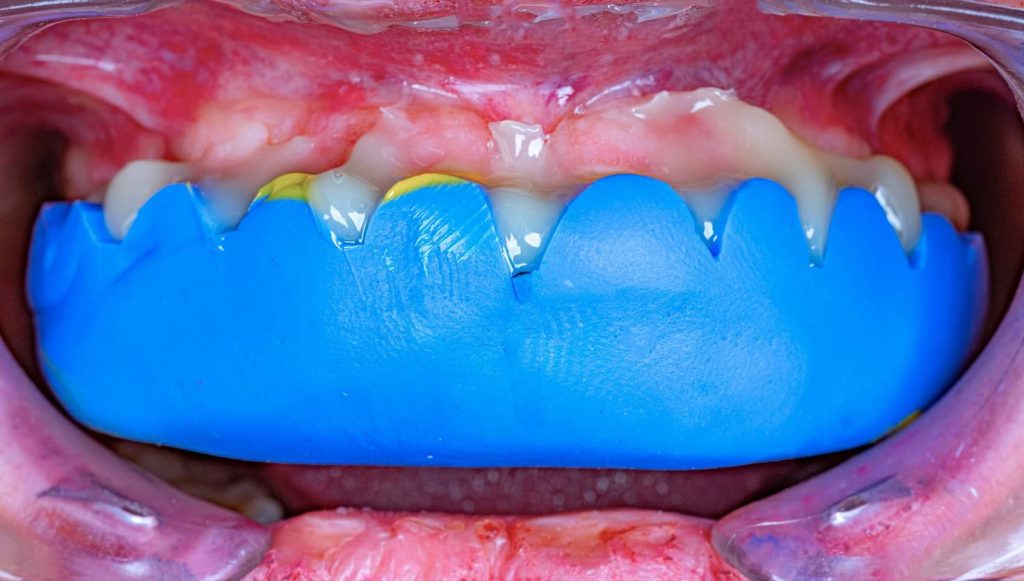

The case presented in this case report is for a 27-years-old female patient with a chief complaint of aesthetic correction for her smile. The patient was unhappy with her smile. After clinical examination, there were previous old composite veneering done poorly and incorrectly to close the multiple interdental spacing. After discussing the various treatment options (i.e., orthodontic treatment, direct, or indirect veneers), indirect ceramic veneering was selected. The step-by-step treatment protocol is presented in the images below.